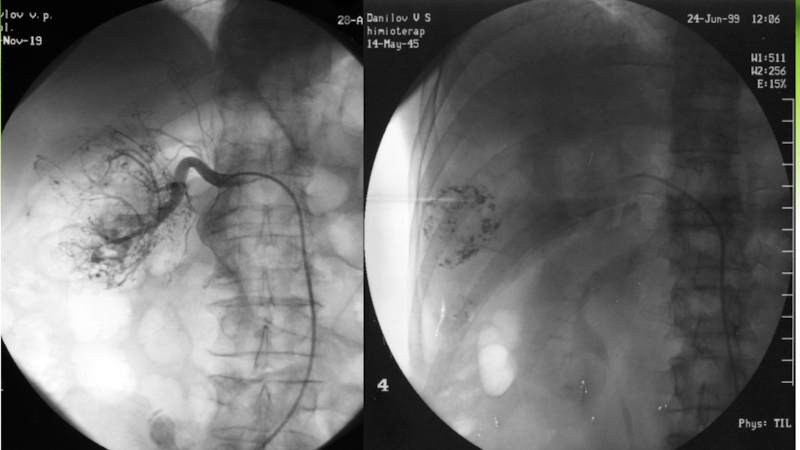

Слайд 38Эндоваскулярная хирургия и онкология

Химиоэмболизация – это метод местной химиотерапии при

различных злокачественных новообразованиях. Суть метода заключается в эмболизации артерии питающей

опухоль эмболизирующим материалом, в составе которого содержится противоопухолевый препарат. Подразделяется на:

Масляную эмболизацию

Эмболизацию микросферами

Слайд 39 Эндоваскулярная хирургия и онкология

Эндоваскулярная хирургия и онкология

Слайд 40Эндоваскулярная хирургия и онкология

Масляная химиоэмболизация – носителем масляный рентгеноконтрасный препарат,

который удерживает высокую дозу химиопрепарата в опухоли в течении нескольких

часов. Не вызывает стойкую ишемию (кислородное голодание) опухоли, т.к. не вызывает необратимую эмболизацию артерии питающую опухоль.

Эндоваскулярная хирургия и онкологияМасляная химиоэмболизация – носителем масляный рентгеноконтрасный препарат, который удерживает высокую дозу химиопрепарата в опухоли